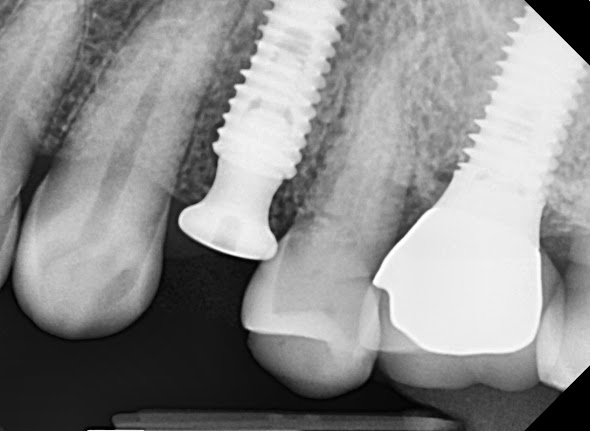

Here's a case of a 57-year-old female patient. She's planning to have an immadeate implatation in there a #24 area.

Afterwards,  bone healing abutment of size 504 was installed.